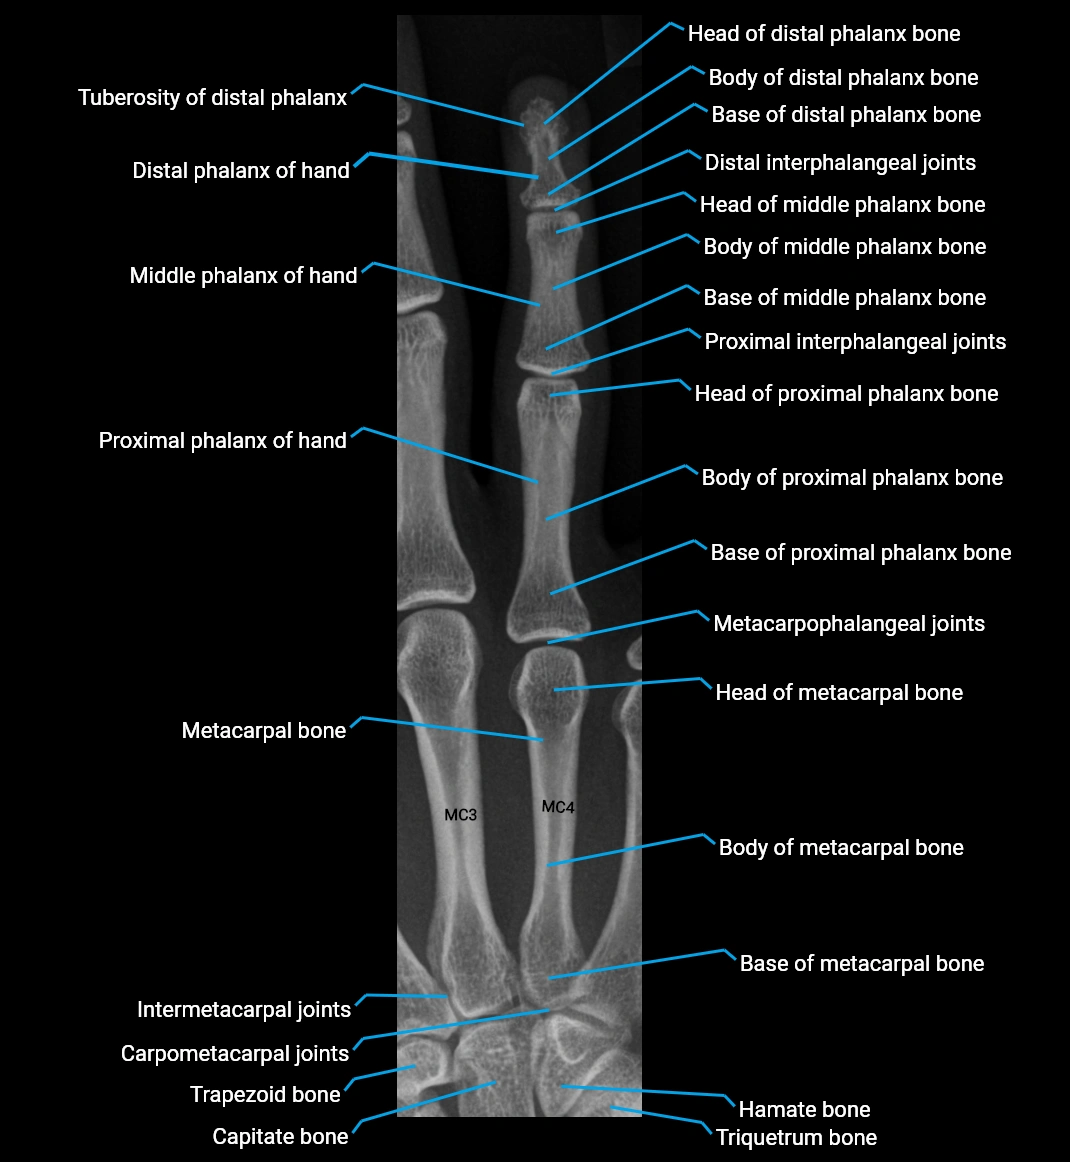

Base of distal phalanx

The base of the distal phalanx forms the proximal articular end of the distal phalanx in each finger. It provides the concave articular surface for the head of the middle phalanx, forming the distal interphalangeal (DIP) joint. The base is essential for finger flexion and extension mechanics and acts as the anchor point for key soft-tissue structures.

It supports the extensor mechanism dorsally, receives the flexor digitorum profundus (FDP) tendon at the palmar surface, and stabilizes the DIP joint through collateral ligaments and the joint capsule. As a compact region bearing both tendon insertions and joint articulation, it is frequently involved in DIP joint injuries, avulsion fractures, and fingertip trauma.

Location and Structure

• Position: Proximal end of the distal phalanx, articulating with the head of the middle phalanx.

• Shape: Concave articular surface covered with hyaline cartilage; dorsal surface blends with extensor expansion; palmar surface thickened for tendon insertion.

• Composition: Thin cortical shell with fatty cancellous bone internally.

Relations

• Dorsally: Terminal extensor tendon

• Palmarly: Flexor digitorum profundus tendon insertion

• Laterally: Collateral ligaments of the DIP joint

• Proximally: Head of the middle phalanx

• Anteriorly (distally): Shaft and tuft of distal phalanx

CT Appearance

Non-Contrast CT:

• Cortex: High-density, sharply defined arc outlining the base

• Marrow: Lower-density cancellous bone